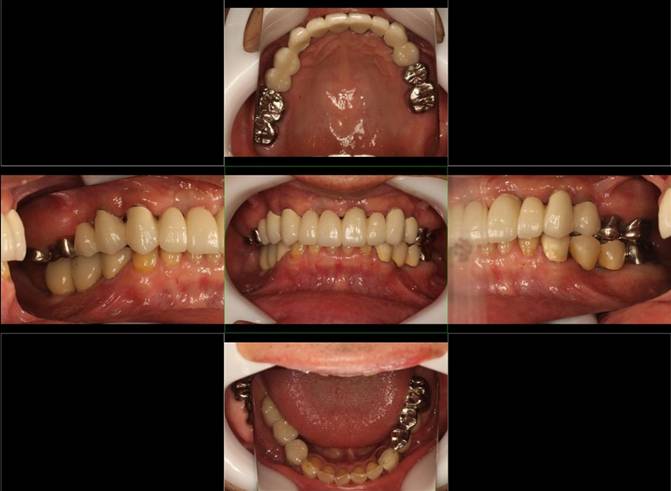

術前。すべての歯が歯周病の末期状態でブリッジ全体がうごいて噛めないとの訴え。右上の犬歯が腫れていました

固定式のブリッジが入っていましたが歯周病で動いています

下顎前歯部には歯石の沈着がみられます

術前パノラマレントゲン写真。根の周りが黒くなり、骨がなくなっていることがわかります

術後。上部構造はハイブリッドレジンです。しっかり嚙めるようになり喜んでいただきました。

治療後。歯周病で失われた骨が回復しています。使用インプラントはスプラインツイストです。

上部構造装着後6年。ハイブリッドレジンを使用したため、少し艶がなくなってきました。上部構造の材料には金属、ハイブリッドレジン、セラミックなどがあります。セラミックはきれいですが欠けやすいため、最近はフルジルコニアを使っています。

上顎 少しすり減ってきました。

下顎。12か月に一度メインテナンスをしています。

インプラント装着後6年。順調に経過しています。12か月毎のメインテナンスをしています。